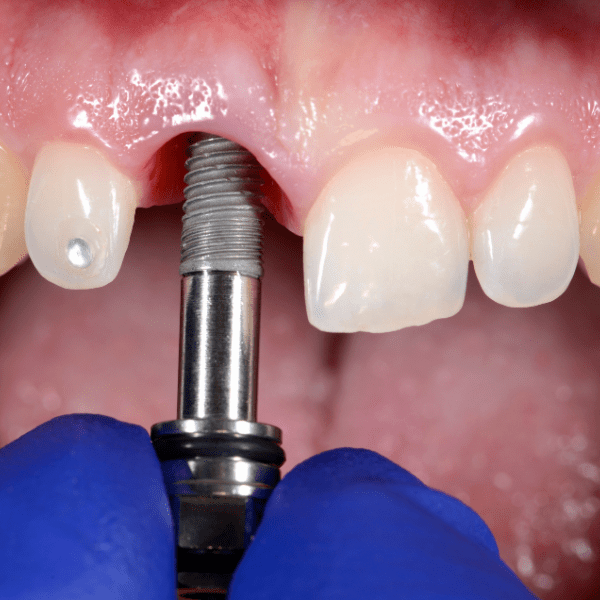

At Summirow Dental Hospital, we offer advanced immediate implant solutions designed for patients who qualify for fast, reliable tooth replacement with natural-looking results. Immediate dental implants are placed directly into the jawbone at the time of tooth extraction.

Instead of waiting weeks or months for healing before implant placement, both steps are completed in a single visit. This technique helps preserve jawbone structure, maintain healthy gum contours, and significantly shorten the overall treatment time- making Summirow a preferred choice for the Best Immediate Dental Implants in Surat.

Every case is carefully evaluated using CBCT imaging and clinical examination to ensure safety and long-term success. Immediate implants may be recommended if:

We use in-house CBCT scans and guided implant planning to achieve precise placement and predictable results.

By preserving gum shape and using digital impressions, we deliver implants that blend seamlessly with your natural teeth.

Immediate placement helps reduce bone shrinkage that typically follows tooth extraction.